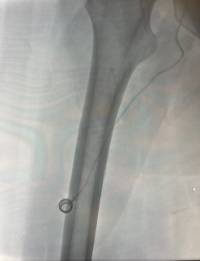

La novedad llega con la incorporación del FICC PORT, un dispositivo similar al PICC PORT, pero que se implanta en el muslo del paciente. Esta ubicación alternativa resulta muy útil en casos en los que las venas de los brazos no pueden utilizarse, ya sea porque están dañadas, agotadas o presentan alguna contraindicación médica.